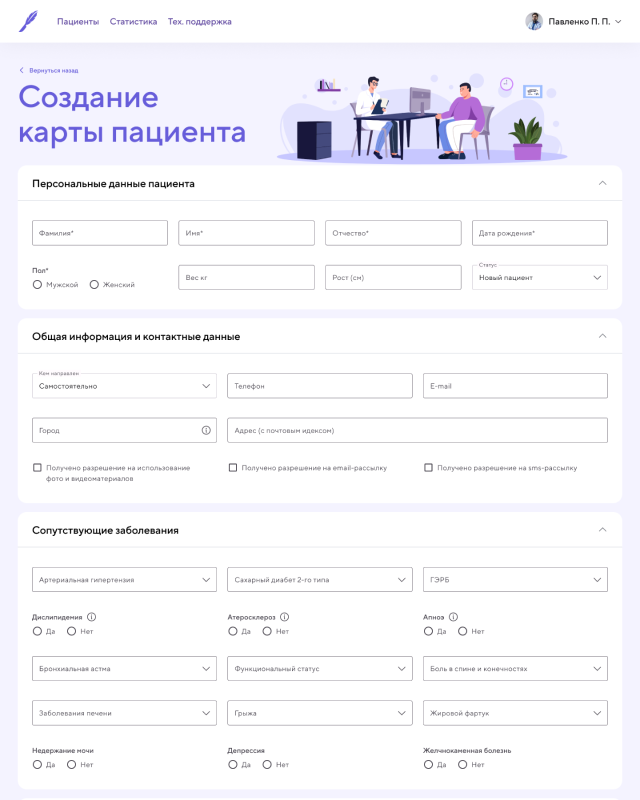

CRM Приложение [ 2022 ]

Работал над CRM-приложением для хирургической клиники по снижению лишнего веса, разработанным с использованием Pug, Vanilla.js и CSS. Приложение предназначено для ведения и учета пациентов, управления операциями и отслеживания результатов лечения.

В рамках проекта реализованы: авторизация и роли пользователей, создание и ведение карт пациентов, продвинутая фильтрация по различным параметрам, а также большие формы для создания операций и наблюдения за пациентами. Для визуализации результатов лечения использовались Chart.js, позволяя наглядно отображать статистику и эффективность применяемых методов.

Я работал над архитектурой интерфейса, реализацией ключевых функций, обеспечением удобного и логичного взаимодействия с данными, а также над оптимизацией форм и графиков для комфортной работы медицинского персонала. Приложение получилось функциональным, наглядным и удобным инструментом для управления пациентами и анализа результатов клиники.